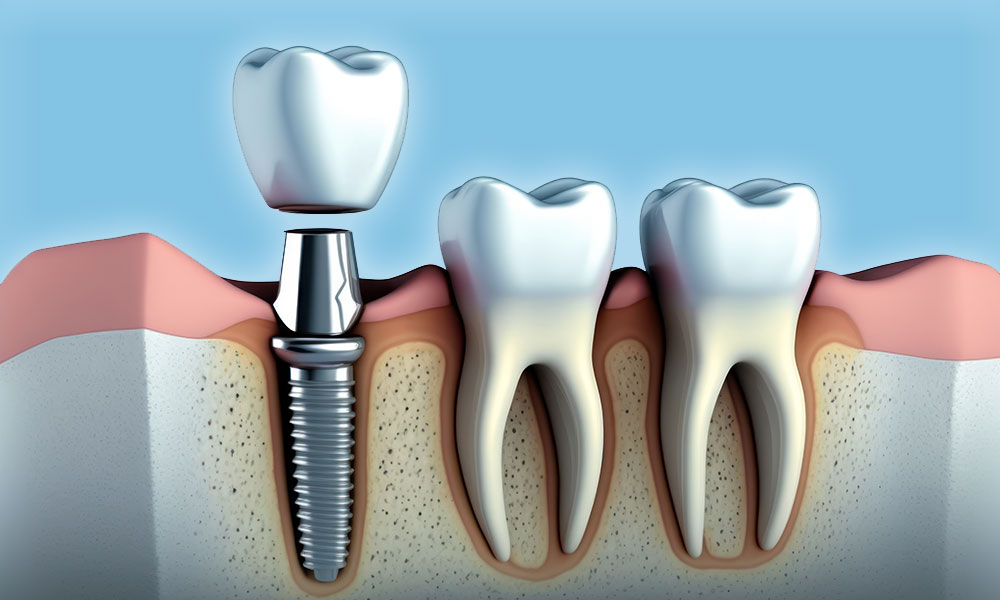

Dental Implants

- Dr Chris Chan has received further training in dental implants from various continuing education courses.

- He is currently attending a Master’s Program in Oral Implantology in Frankfurt.